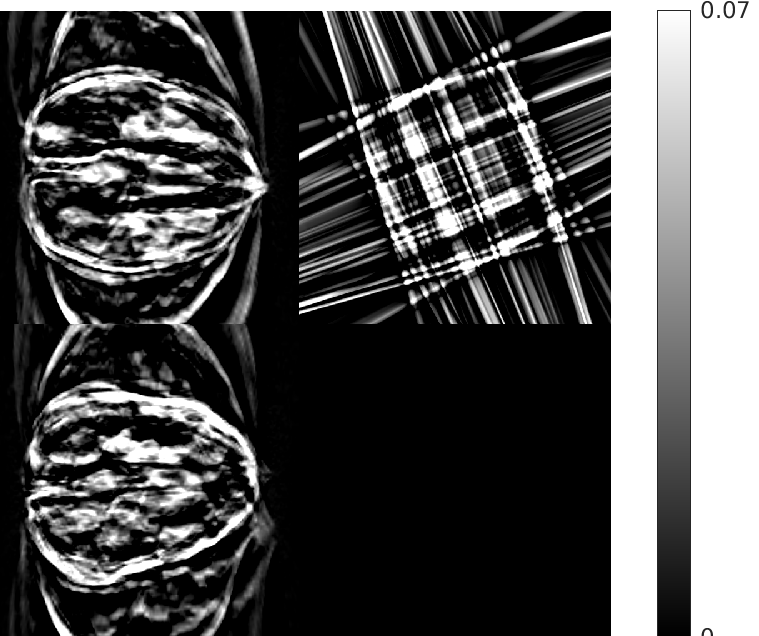

Fig. 4 shows the results of the intermediate steps of the first stage of our reconstruction for walnut 2 (8 views) in the test dataset. While the patch-based destreaking compensates for the blurring introduced by the EP-regularized reconstruction and ‘fills-in’ details in the reconstructed volume, the data-consistency plays a key role in mitigating hallucinations introduced by the CNN, and reinforces image features that are consistent with the acquired measurements.

| Input EP Recon. | Post CNN-based Destreaking | Post Data-consistency |

![]() |

| (NMAE:0.45) | (NMAE:0.38) | (NMAE:0.32) |